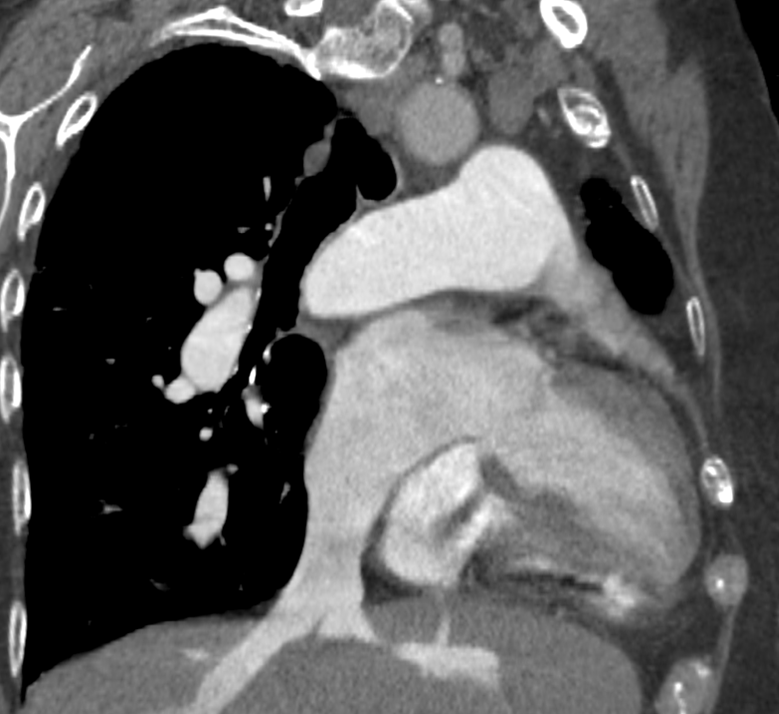

Left atrium enlargement

The diameter measurements of the left atrium on CT axial images should be determined as the largest anterior-posterior diameter. It is a continuous, metric variable.